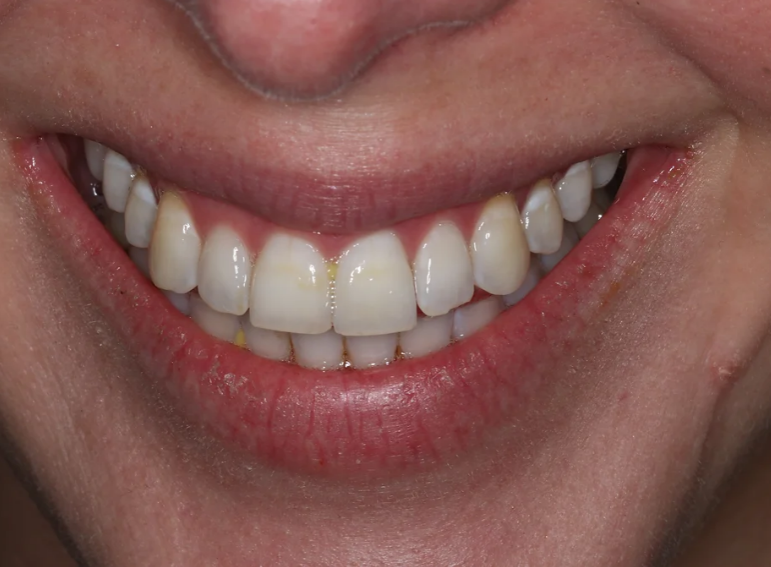

Root canal treatment and combined internal and external whitening.

"Such a great place. Friendly, professional and talented staff. They turned my horrible brown front tooth into something white and beautiful. I can now smile…”